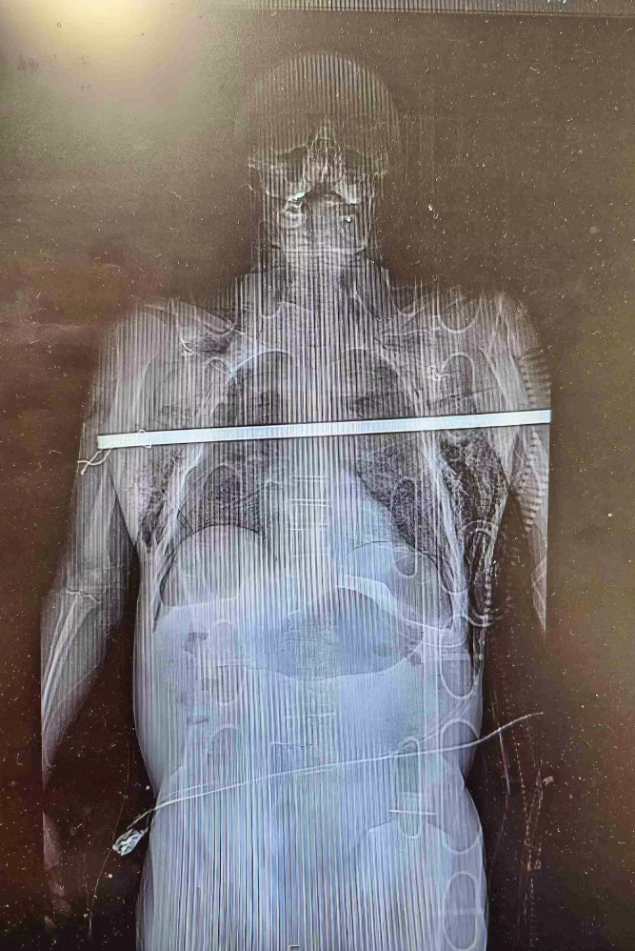

Die Röntgenbilder zeigen Schreckliches: Eine Metallstange bohrt sich nach einem unglücklichen Sturz quer durch den Oberkörper eines Mannes.

Die Stange habe quer die Brusthöhle durchdrungen, beide Lungenflügel durchstoßen und sei nur um wenige Millimeter am Herzen und anderen lebenswichtigen Organen vorbeigeschrammt, teilte das Universitätskrankenhaus im tschechischen Olmütz am Dienstag mit. In einer fünfstündigen Notoperation hätten die Ärzte dem Patienten das Leben gerettet.

Bevor der Rettungsdienst den Patienten ins Krankenhaus bringen konnte, mussten erst Feuerwehrleute anrücken. "Mit einer Hydraulikschere zwickten sie beide Enden der Stange ab, damit ich überhaupt in den Rettungswagen gepasst habe", berichtete der Patient später. "Es hätten wenige Millimeter gereicht, und dem Mann wäre nicht mehr zu helfen gewesen", sagte Chirurg Martin Kalab. Die Mediziner setzten demnach eine Operationsmethode ein, die sonst eher bei Organtransplantationen verwendet wird.